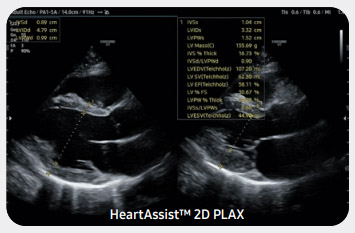

Автоматизированный инструмент подготовки отчетов для кардиодиагностики

Функция HeartAssist™, основанная на технологии глубокого обучения, автоматически определяет по ультразвуковому изображению проекции измерений для кардиодиагностики и предоставляет результаты измерений.